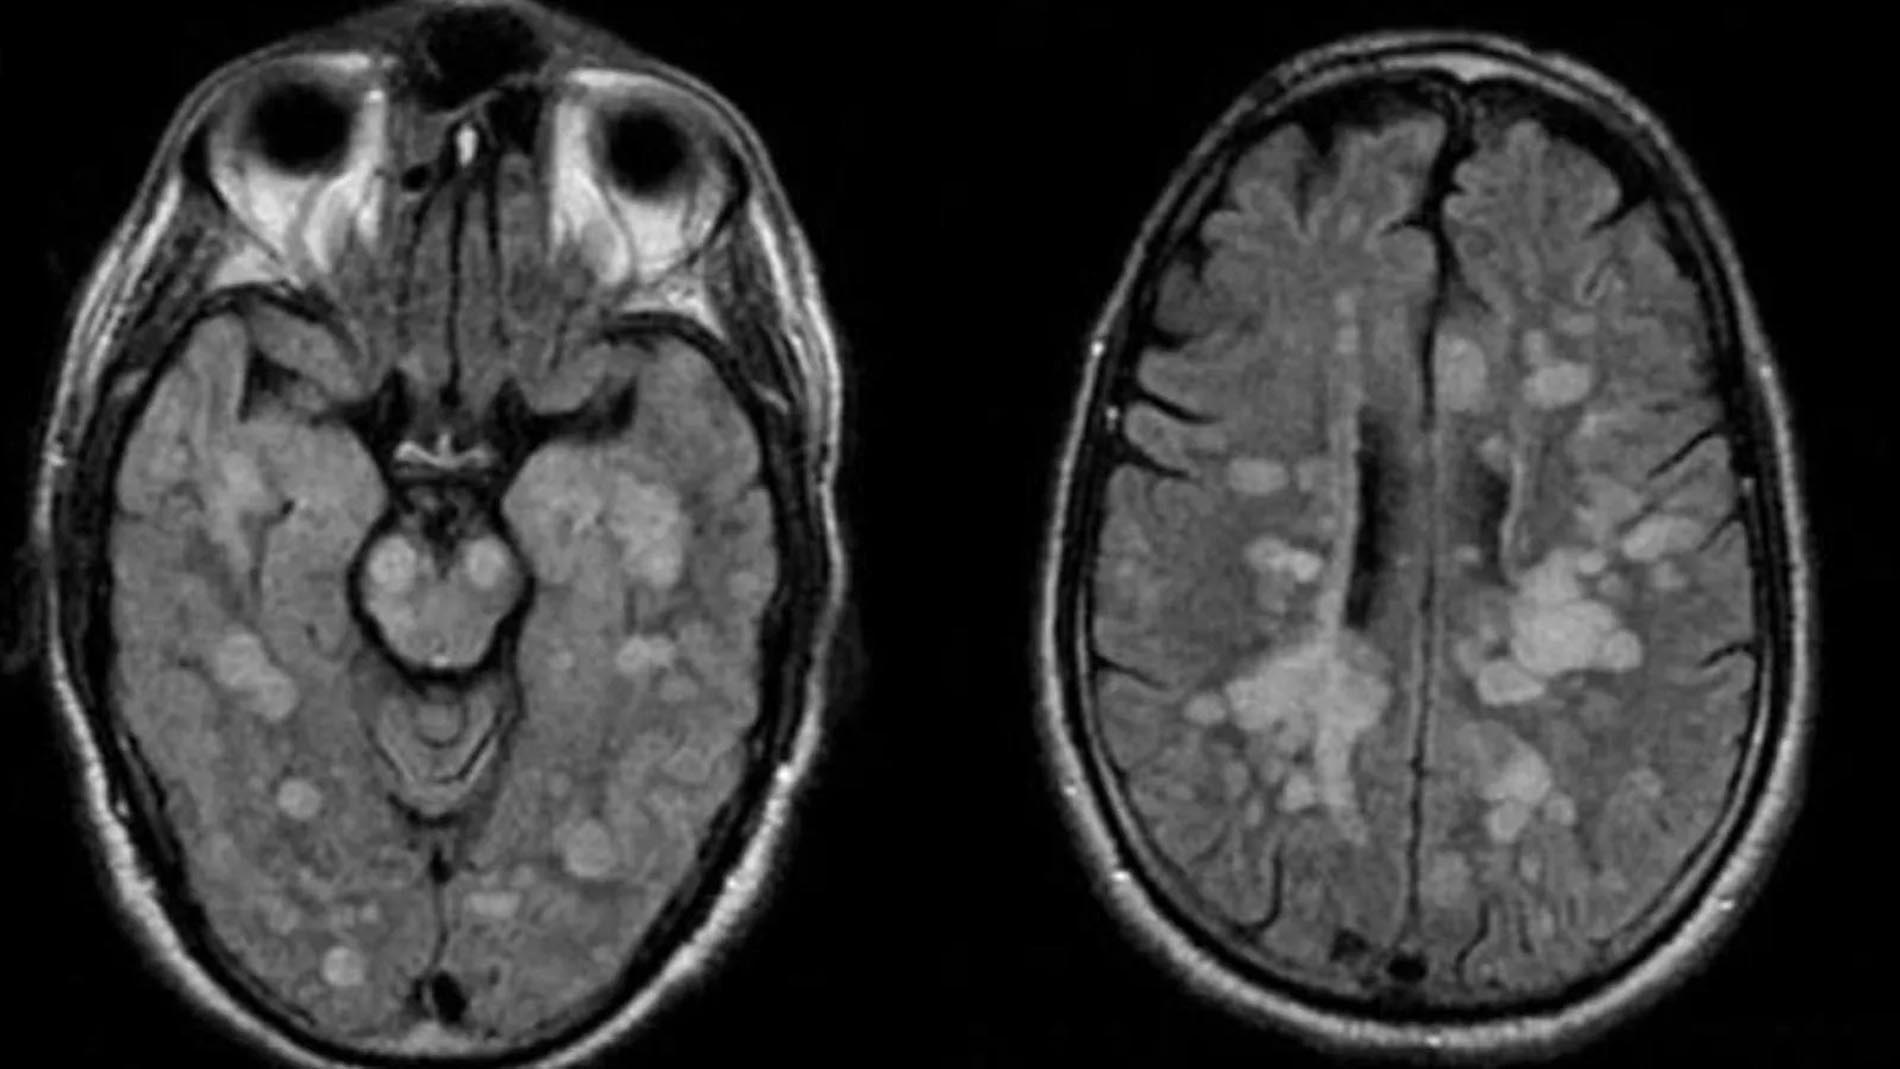

Talihsiz çocuğa vücudun bağışıklık sistemine omurilik ve beynin şişmesine neden olan nadir bir akut yayılmış Ensefalit (ADEM) teşhisi koyuldu.

Braun’un Akut dissemine ensefalomyelit (ADEM) santral sinir sistemi bozukluğuna yakalandığı bildirildi. Tıp uzmanları, Haziran ayında koronavirüs ve ADEM arasındaki bağlantıyı kurmaya başladıklarını açıklamıştı.